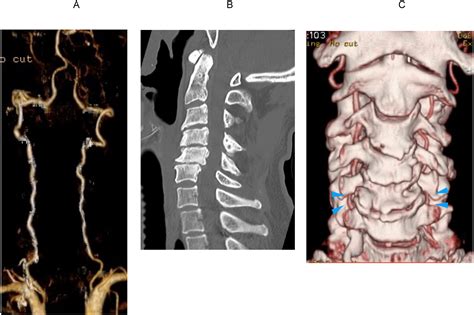

• CT Angiography (CTA): This provides a detailed 3D view of the blood vessels in the neck and brain, identifying blockages quickly.

• Digital Subtraction Angiography (DSA): Considered the "gold standard," this invasive procedure involves injecting contrast dye to map the arteries with high resolution.